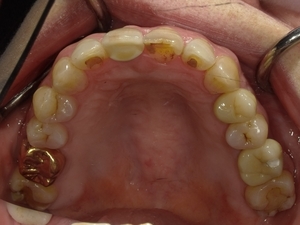

ガタガタとした歯並びや八重歯(叢生)CASE75